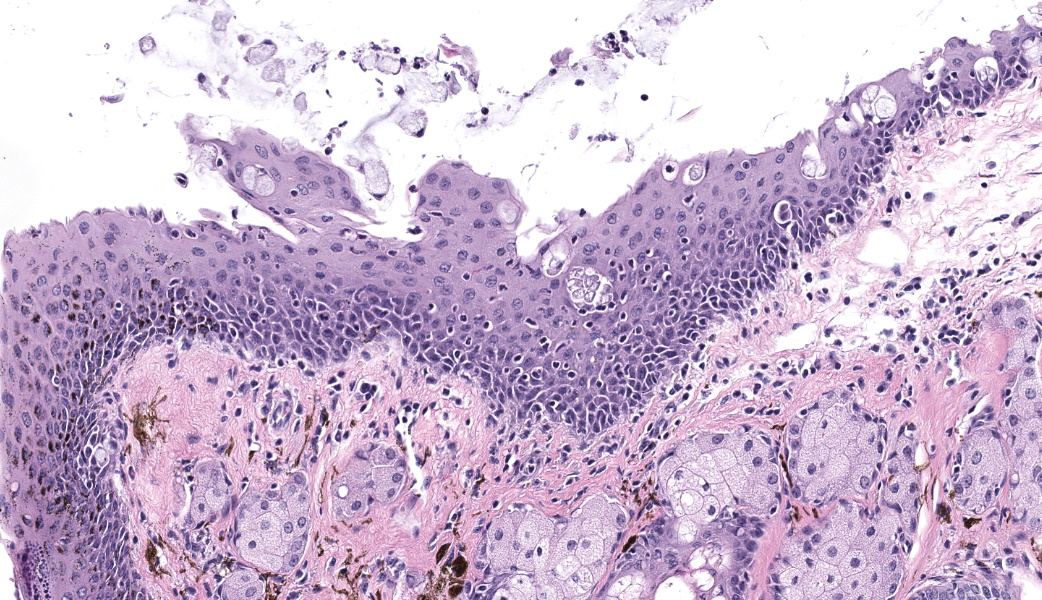

Bilaterally or unilaterally*, the eyelids contained locally extensive epidermal acanthosis and ortho to parakeratotic hyperkeratosis of varying severity. This was accompanied by epithelial erosion and mild serocellular crusting. There was mild to moderate mixed neutrophilic to lymphocytic inflammation within the conjunctiva and eyelid sebaceous glands (Meibomian glands). Focally there was occasional dilation and mild degeneration of Meibomian gland acini or ductules. The cornea, lens, iris, retina, optic nerve and other interior structures of the eyes were normal.

- Eyelids: Blepharoconjunctivitis, neutrophilic, with epidermal acanthosis, erosions, and ortho to parakeratotic hyperkeratosis, unilateral to bilateral, moderate, chronic.

- Eyelid: Blepharoconjunctivitis, unilateral, lymphocytic and neutrophilic, chronic, diffuse, mild, with epidermal hyperplasia and erosion.

- Eyelid, Meibomian gland: Adenitis, lymphoplasmacytic, chronic, focal, mild.